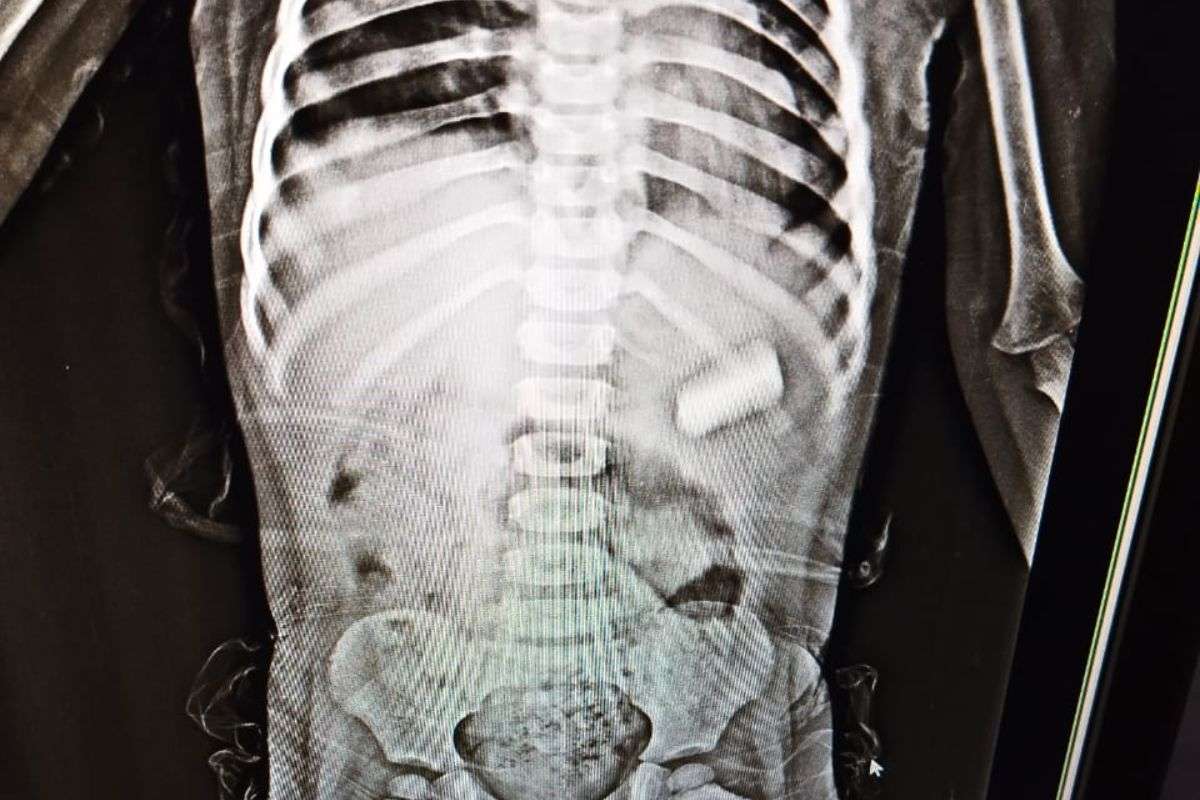

पटना सिटी के एक परिवार की सांसें उस समय अटक गईं, जब 3 साल की मासूम बच्ची ने खेल-खेल में पेंसिल बैटरी निगल ली. परिजनों ने पहले केला खिलाने जैसे कई घरेलू नुस्खे अपनाने की कोशिश की, पर कोई फायदा नहीं हुआ. बच्ची की हालत बिगड़ती देख परिजन उसे तुरंत सत्यदेव सुपर स्पेशियलिटी हॉस्पिटल लेकर पहुंचे.

अस्पताल में आपातकालीन स्थिति में डॉक्टरों की टीम ने तुरंत उसका इलाज शुरू कर दिया. वरिष्ठ यूरोलॉजिस्ट और हॉस्पिटल के डायरेक्टर ने बताया की डॉक्टरों की टीम ने दूरबीन (एंडोस्कोपी) तकनीक के माध्यम से बैटरी को सफलतापूर्वक बाहर निकाला. बच्ची को एक दिन ऑब्जर्वेशन में रखा गया और अब वह पूरी तरह स्वस्थ होकर घर लौट चुकी है.

इस पूरे मामले को लेकर डॉ. अमृता ने बताया कि “बच्ची महज तीन साल की थी, जिसके कारण यह प्रक्रिया काफी चुनौतीपूर्ण थी. अगर बैटरी पेट में रह जाती, तो उससे निकलने वाला जहरीला पदार्थ पूरे पेट में फैल सकता था, जो जानलेवा साबित होता.” उन्होंने बताया कि इतनी कम उम्र में एनेस्थीसिया देना भी एक जोखिमपूर्ण कदम था, लेकिन टीम ने सावधानी से सफल ऑपरेशन किया.